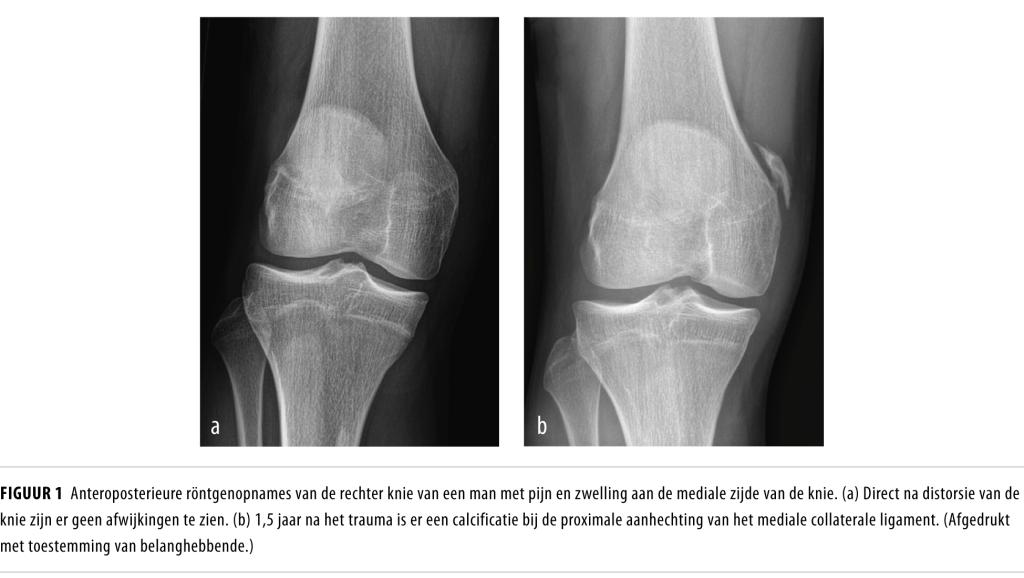

Een 19-jarige man kwam naar de polikliniek Orthopedie vanwege pijn en een zwelling aan de mediale zijde van zijn rechter knie. Hij had vooral last bij sprinten en trappen tegen een voetbal. Hij voelde een harde verdikking aan de binnenzijde van de knie. Patiënt had 1,5 jaar eerder 2 maal een distorsie van de rechter knie doorgemaakt tijdens voetbal, waarbij destijds een mediaal collateralebandletsel graad 1 werd gevonden. Een röntgenfoto van de knie toonde toen geen afwijkingen (figuur a).Bij lichamelijk onderzoek vonden wij geen hydrops in de knie. De knie had een flexie van 120 graden, een extensie van…